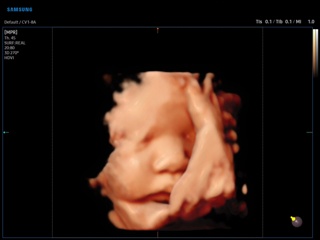

Atlas of ultrasound images - obsterics

In the section "Оbsterics" of atlas the results of ultrasonic examinations of pregnant women with different durations of gestation are represented. Here you can see images of internally organs, cerebrum, cordis and the sex of the fetus, the sonograms of multiple pregnancy, the blood flow in placenta and umbilical cord, defects of fetal`s development, etc.